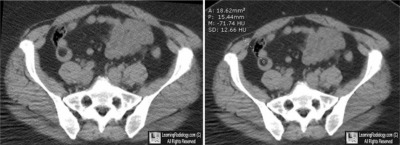

Case of the Week 533

• 51 year-old with intermittent RLQ pain

Axial CT Image of Pelvis with Region of Interest

4. Small Bowel Lipoma

Small Bowel Lipoma

• Most lipomas of the GI tract occur in the colon, the small bowel being the 2nd most common site and accounting for about 25%

• Most small bowel lipomas are found in the ileum

• Most often submucosal and may be pedunculated